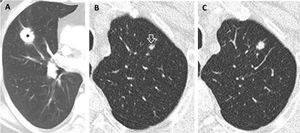

(A–C). Prevalent and pseudo-incidental screen-detected LC at baseline LDCT. Stage IA adenocarcinoma in a 60-year-old man from ITALUNG (A) appearing at baseline LDCT as a large (26mm in mean diameter) solid nodule in the right upper lobe (*). Pseudo-incidental stage IA squamous cell carcinoma in a 67-year-old man from ITALUNG (B and C) appearing at baseline LDCT (B) as an infra-threshold (5.2mm in mean diameter) solid nodule in the left anterior lobe (white empty arrowhead) and showing growth (10mm in mean diameter) at the first annual repeat (C).